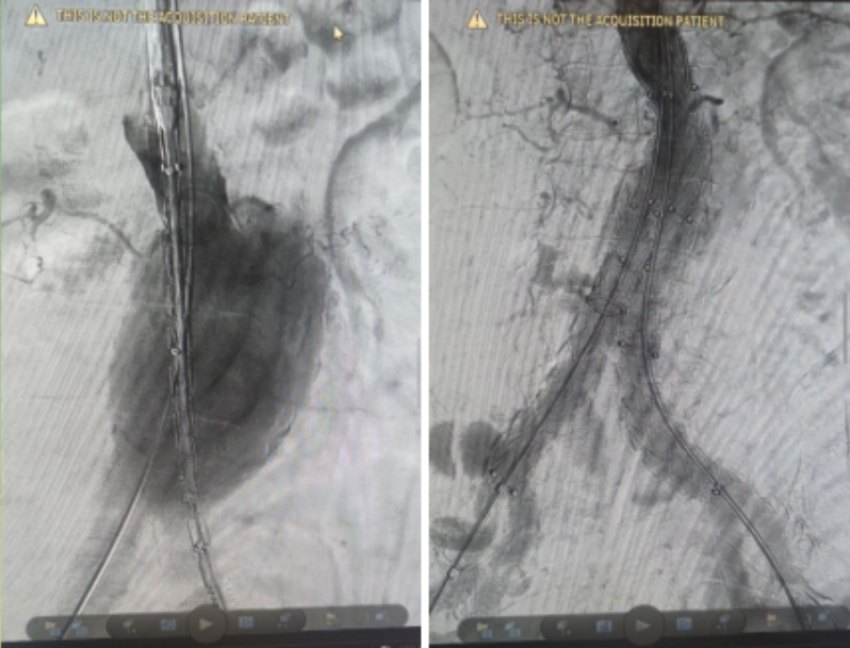

Волгоградская областная клиническая больница №1 вновь продемонстрировала высочайший класс медицины, успешно проведя сложнейшую операцию по спасению пациента с жизнеугрожающей аневризмой брюшной аорты. Уникальное эндоваскулярное вмешательство с использованием стент-графта открывает новую эру в лечении сосудистых патологий региона.

Пациент, пожилой мужчина старше 70 лет, столкнулся с серьезнейшей угрозой – аневризмой брюшной аорты огромного размера. Состояние осложнялось симптомами сдавления соседних органов, что требовало незамедлительного вмешательства. Однако, учитывая возраст больного и наличие у него множества тяжелых хронических заболеваний, традиционная открытая операция несла в себе неприемлемо высокий риск. Именно поэтому команда высококвалифицированных сосудистых хирургов Волгоградской ОКБ №1 приняла смелое решение о проведении передовой малотравматичной операции.

Основной задачей операции было предотвращение катастрофического разрыва аневризмы, который в такой ситуации является смертельным. И современная медицина предложила элегантное решение.

Стент-графт – это настоящее чудо инженерной мысли в медицине. Он представляет собой хитроумное сочетание двух элементов:

Стента - каркас из металла или полимеров, который, как надежная поддержка, восстанавливает и удерживает ослабленную стенку сосуда.

Графта - специальная оболочка (тканевая или синтетическая), которая придает всей конструкции дополнительную прочность и герметичность.

Вся эта конструкция вводится в аневризму через крошечный прокол, как бы «зашивая» ее изнутри. Она создает новый, прочный и безопасный путь для кровотока, полностью исключая нагрузку на пораженный участок аорты. Таким образом, функция жизненно важного магистрального сосуда восстанавливается, а угроза разрыва и опасных осложнений устраняется.